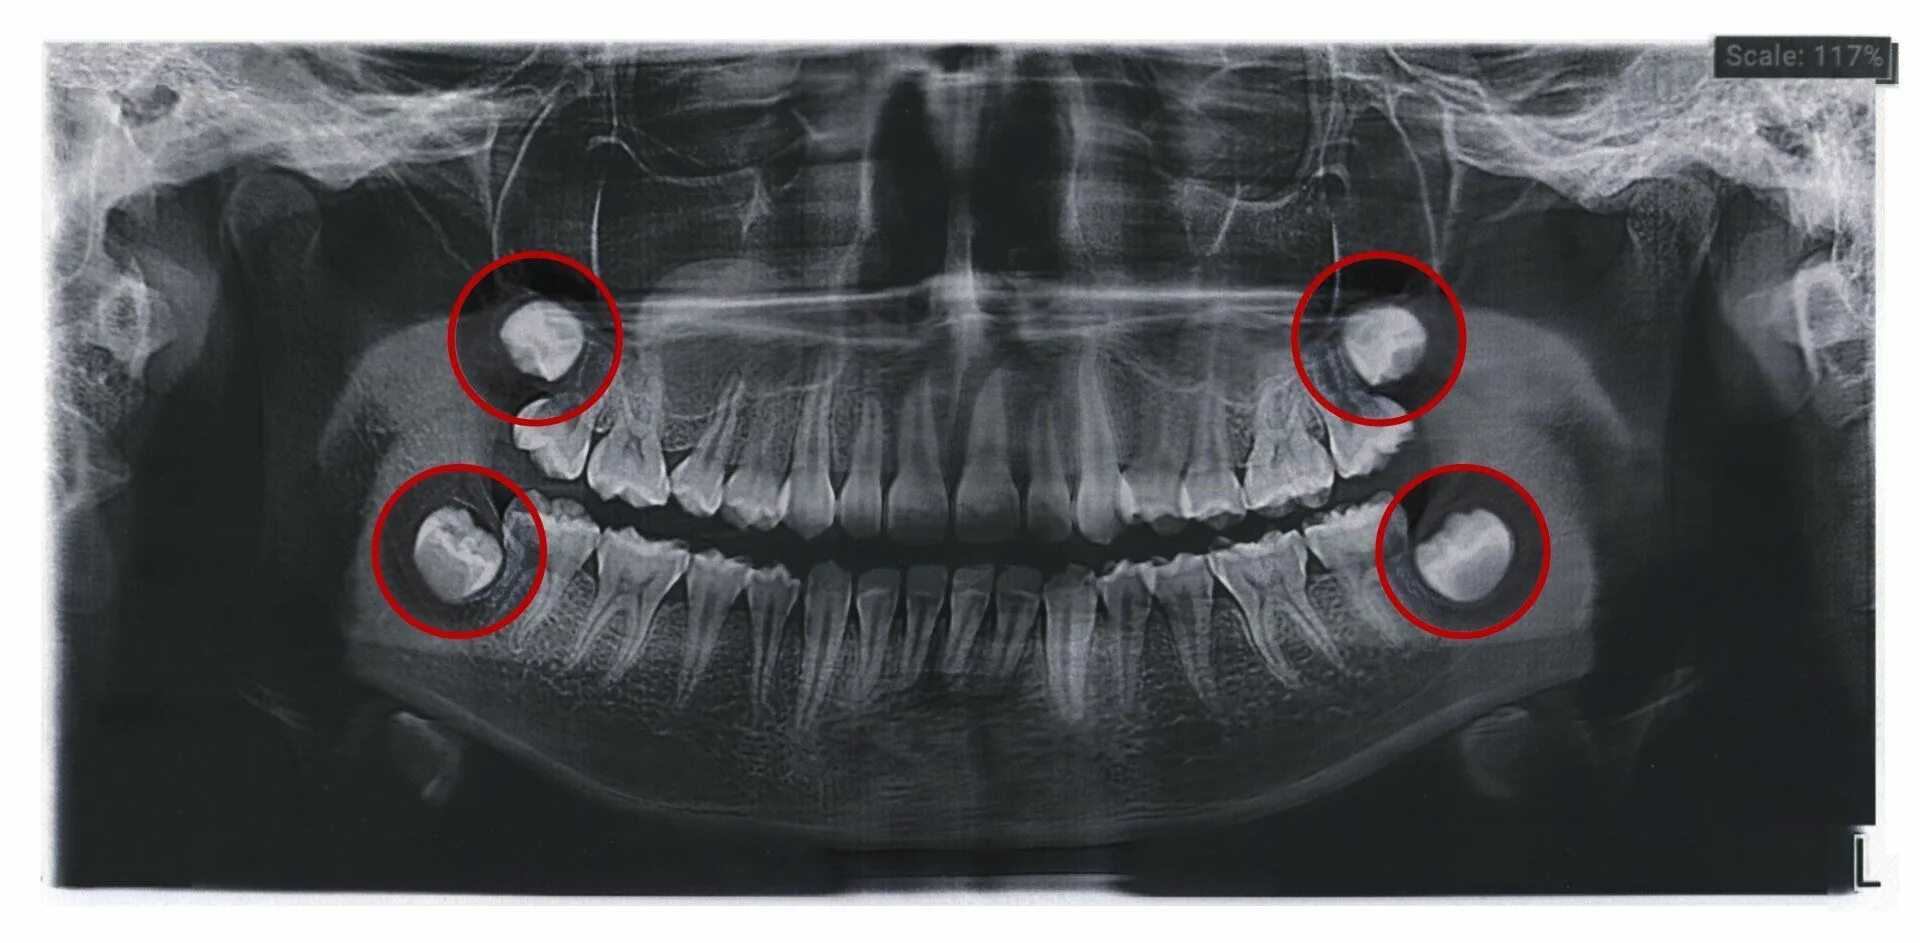

Как выглядит зачатка